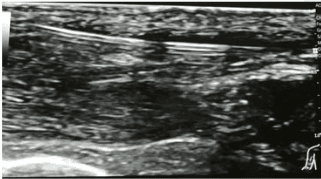

El uso de la visualización ecográfica de la canalización se puede desarrollar en cualquiera de sus planos (eje transversal o eje longitudinal) dependiendo de la destreza y las preferencias del operador, pero es común el desarrollo mediante eje transversal (o fuera de plano) de las punciones en territorios periféricos debido al menor espacio y la mayor dificultad para la visualización completa de la trayectoria del vaso. En el caso de accesos centrales, como es el caso del tronco braquiocefálico, el eje longitudinal (o en plano) es uno de los recursos más utilizados para evitar el riesgo de punción a doble pared.

Mediante esta técnica se asegura la correcta canalización del vaso objetivo y se evita la punción accidental de vasos arteriales, nervios o tejidos adyacentes. El desarrollo de la técnica ecoguiada dinámica permite aumentar las tasas de acierto y minimizar los daños producidos al vaso.